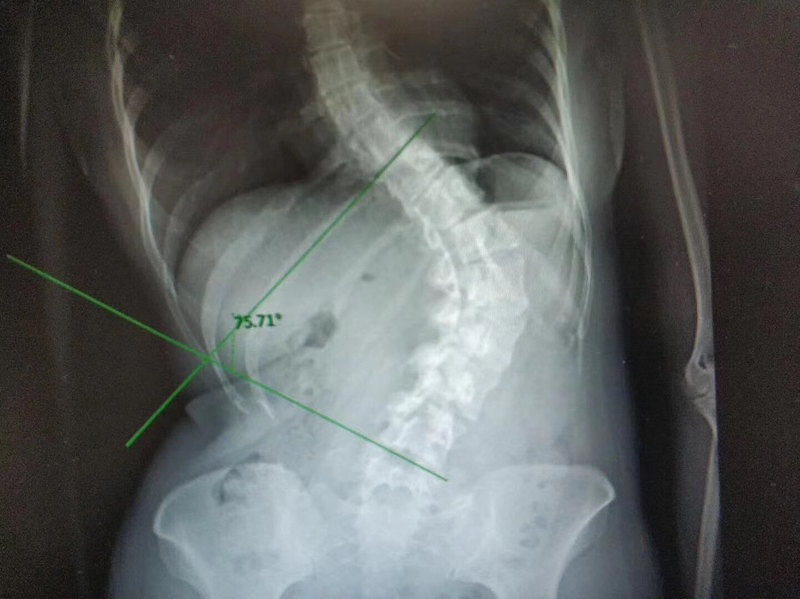

前些天有同行感慨,自己帶的實習(xí)生本身就是醫(yī)療從業(yè)人員,卻很少關(guān)注個人的身體變化,在老師的催促下完成了一張全脊柱片才發(fā)現(xiàn)自己的脊柱已經(jīng)變形,出現(xiàn)了嚴(yán)重的側(cè)彎。有時候作為醫(yī)務(wù)人員真正感到自己弱小的時候就是那一瞬間,健康科普任重而道遠(yuǎn),從業(yè)者尚且如此,何況病人和家屬呢?